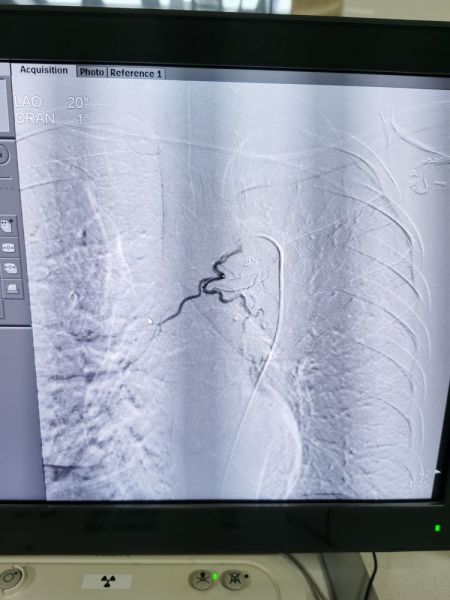

左下支气管动脉发现多个出血灶

栓塞后病灶出血停止